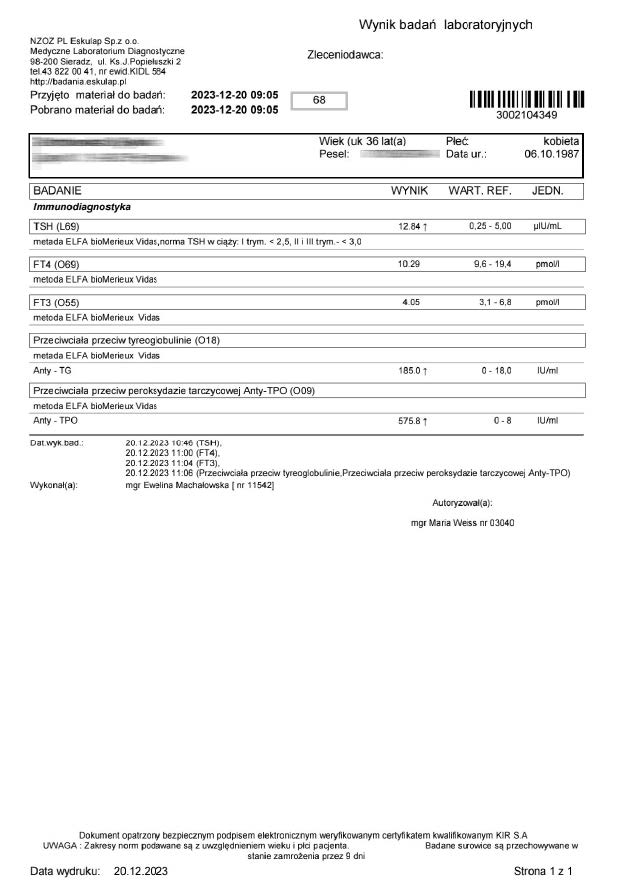

Kobieta lat 36 zastosowała terapię preparatem ze względu na pogarszające się samopoczucie i wysoki wynik TSH oraz anty-tpo jednoznacznie wskazujący na niedoczynność tarczycy. Brak zastosowanej farmakologii lewotyroksyną. Po zaledwie 12 dniach stosowania preparatu odnotowano znaczny spadek parametrów tarczycy oraz przeciwciał.

Wyniki odwrócenia procesów autoimmunologicznych wykraczają poza typowe leczenie i wykazują, że preparat wzmacnianjąc i stymulując mitochondria działa poprzez energetyczną optymalizację, co umożliwia długoterminową regenerację w różnych grupach wiekowych.